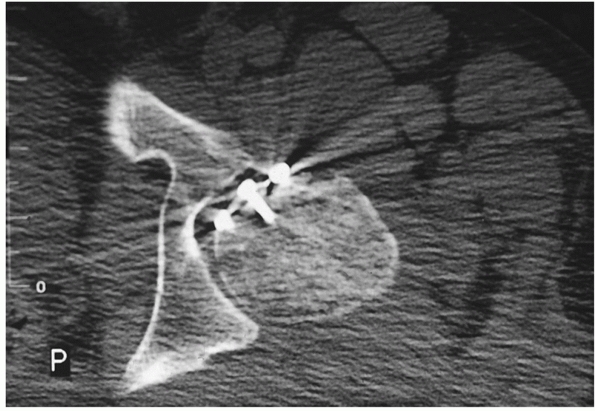

![]() |

|

FIGURE 46-5

A 53-year-old woman with a posterior hip dislocation demonstrating fragments in the joint prior to hip reduction and an inferior femoral head fracture (A). The postreduction AP and Judet views (B-D) demonstrate a widened joint space compared with the normal side and an incongruent reduction. Note that there are fragments both superior and inferior in the joint and that there is a loss of parallelism of the femoral head and acetabular articular surfaces. |